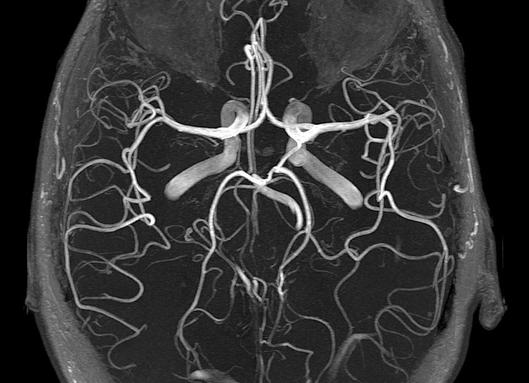

Сразу опровергнем ошибочное мнение, отметив, что для пациента это абсолютно безвредная, безболезненная процедура, проводить которую с промежутками можно не один раз. Её практикуют как с использованием контрастного раствора, так и без него. Электромагнитные волны помогают получить двухмерные и трёхмерные фотографии мозговых сосудов в разнообразных проекциях. Именно по этим фотографиям опытные специалисты делают вывод о том, есть ли в организме человека заболевания, какие именно, или же их нет.

Исследование в формате МРТ-ангиографии позволяет с мельчайшими деталями разобраться с состоянием его артерий и вен. Очень чёткие снимки отражают все внутренности сосудов, включая поверхности стенок вплоть до микроскопических новообразований. Помимо того, функциональный формат 3D проявляет внутри мозговых сосудов систему его кровотока, адекватно отражая его непростой процесс, выявляет даже незначительные отклонения от нормальных параметров. Внимательно изучив эти отчётливые снимки, сопоставив их с результатами других обследований пациента, врач получает объективную картину всего происходящего внутри сосудов и затем сможет определить наличие тромбозов, аневризмов, атеросклероза, расслоений и прочих аномалий, отклонений от нормы. Стоит заметить, что контрастные вещества применяются, как правило, в очень сложных случаях, если есть метастазы, опухоли. На основании того, что показывает исследование, врач принимает соответствующее решение о дальнейшем лечении заболевания.

Магнито-резонансная ангиография. Суть этого метода состоит в том, что сигналы от неподвижных тканей и крови отличаются, и томограф передает это в разные сигналы. Благодаря магнито-резонансной ангиографии врач получает качественные трехмерные изображения сосудов головного мозга, а также может судить о степени их поражения.

Снимок сосудов головного мозга при мрт ангиографии

МРТ сосудов головного мозга показывает многие особенности строения сосудов, их возможные отклонения от норма.

Врач может увидеть на снимках, полученных при МРТ:

• срезы сосудистых стенок (они получаются очень тонкие, так что специалист без проблем может увидеть, как изменяется их структура и как от этого страдает кровопитание головного мозга);

• отдельные сосуды головного мозга (направленное воздействие магнитного поля способствует тому, что терапевт видит не только расположение патологического очага, но и его размеры);

• увидеть тромб, его локализацию и размеры, что очень важно при диагностике тромбоза, инсульта и проч.);

• собрать необходимую информацию об особенностях морфологического строения сосудов головного мозга;

• МРТ сосудов головного мозга также показывает аневризму, ее локализацию, размер и проч.